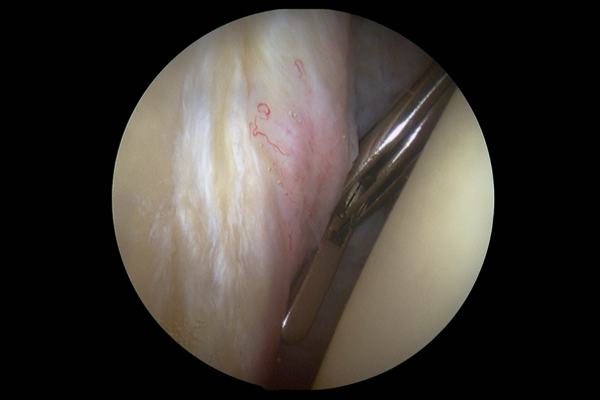

Arthroscopic Surgery